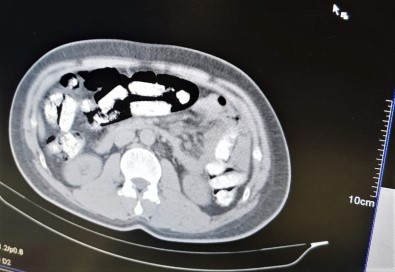

Erzincan’da narkotik polislerinin yaptığı yol uygulaması sırasında durdurulan otobüste, uyuşturucuyu midesine gizleyen İran uyruklu 1 kişi tutuklandı.

Abdulmennan S. hakkında TCK 188 suçundan yapılan tahkikat sonrası sevk edildiği mahkemece tutuklanarak cezaevine teslim gönderildi.